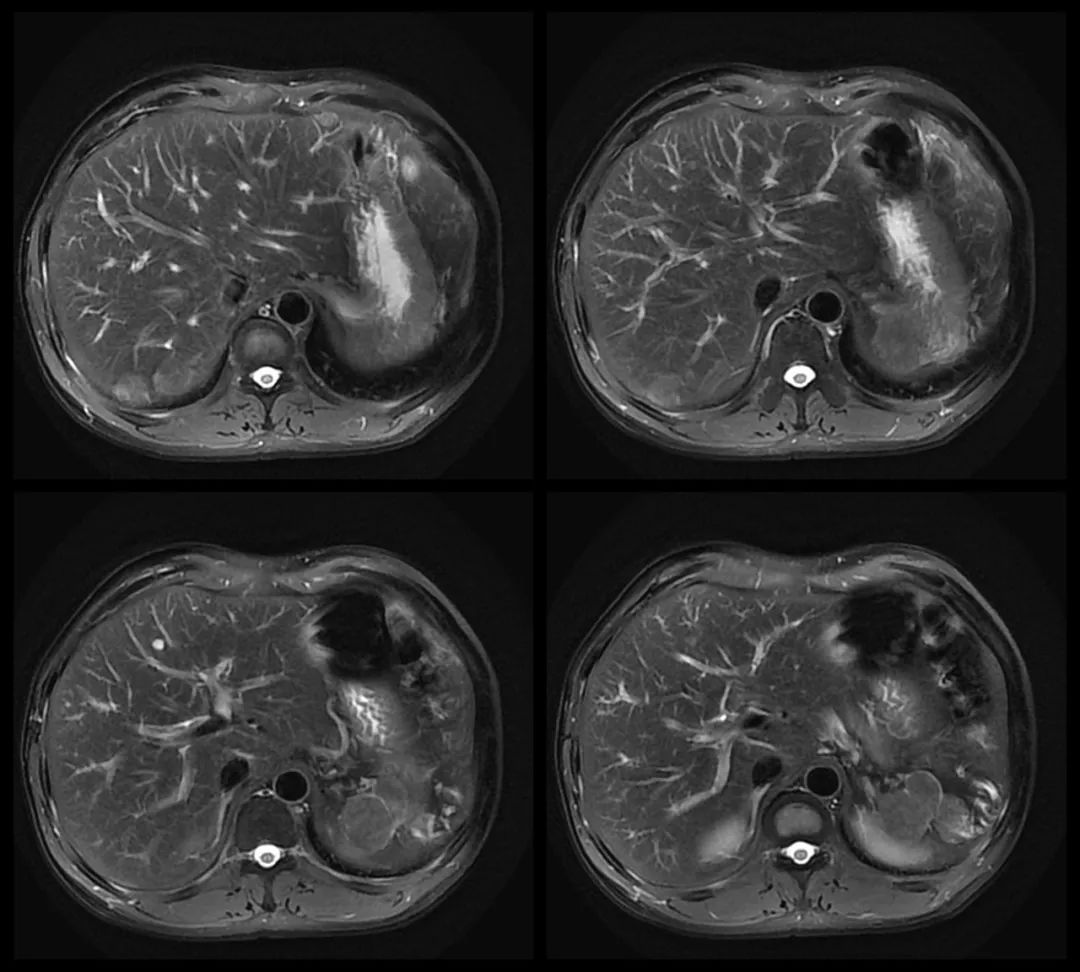

MRI:

MR:多数表现为 T1WI 稍低信号,T2WI 中高信号,与正常脾组织信号相似。增强扫描动脉期、门静脉期和延迟期均为高信号。